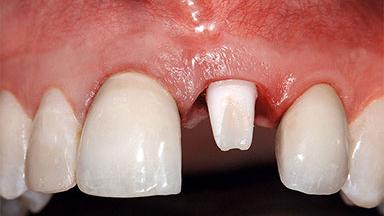

Replacement of a Missing Upper Left Central Incisor: Late Placement of an RC Bone Level Implant, CAD/CAM Zirconia Abutment

Eduardo R Lorenzana, Jason R Gillespie

A healthy 37-year-old female patient was referred for a consultation on the replacement of missing tooth 21 with an implant-supported restoration. She stated that several years previously the tooth had been traumatically avulsed following a motor vehicle accident. The tooth was replaced with a three-unit fixed partial denture (FPD) immediately afterwards. Over time, she became disillusioned with the FPD and looked for a different option, including orthodontic therapy. She presented still in her orthodontic appliances, with the pontic sectioned free from the FPD but attached to the archwire. Her orthodontist felt that orthodontic treatment had been successfully completed, but nevertheless referred her before removing the appliances in case adjustments were necessary.